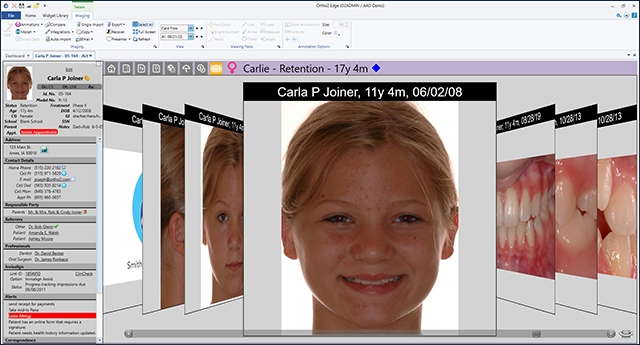

Easily Incorporate into Your Work Day

Quick and easy photo imports are just the start of the streamlined process for Edge Imaging. Images appear throughout the program so you can quickly identify patients, view photos in the Treatment Hub, and quickly email images to other professionals.